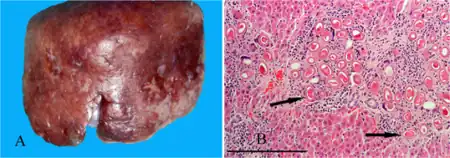

| a,b)Hepatic capillariasis | |